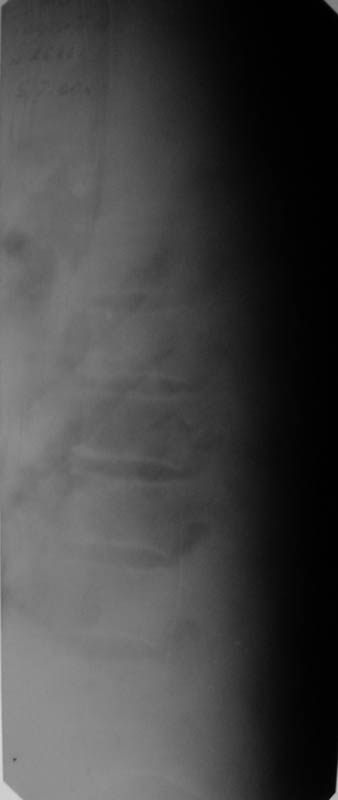

В настоящее время жалобы на отсутствие чувствительности в нижних конечностях, невозможность самостоятельной ходьбы (передвигается на кресле). КОНСУЛЬТАТИВНОЕ ЗАКЛЮЧЕНИЕ ЯМР-ТОМОГРАФИЧЕСКОГО ИССЛЕДОВАНИЯ Проведена МР_томография грудного отдела позвоночника в сагиттальной проекции, с различной степенью контрастирования тканей, в режимах Т1 и Т2 В/И + МР-миелоурография. Визуализированы: спинной мозг с уровня D1 до уровня D12, тела позвонков D1-D12, межпозвонковые диски. Спинной мозг на уровне D4-D6 истончен с неровными нечеткими контурами, гетерогенной структуры, умеренно пониженной интенсивности на Т1 В/И, без очаговых изменений. Отмечается клиновидная деформация тела D5, снижена высота тела D4, структура его гетерогенная. Обращают внимание выраженные дегенеративные изменения дисков в грудном отделе позвоночника: снижение их высоты, изменение структуры изображения за счет исчезновения высокоинтенсивного сигнала от ядер. При исследовании в режиме МР-миелоурографии ликворный сигнал на уровне D4-D5 почти прерывается, интенсивность его существенно снижена.

ЗАКЛЮЧЕНИЕ: ПОСЛЕДСТВИЯ КОМПРЕССИОННОГО ПЕРЕЛОМА ТЕЛА D4-D5 С КОМПРЕССИЕЙ СПИННОГО МОЗГА. МРТ-ПРИЗНАКИ МИЕЛОПАТИИ И РУБЦОВО-СПАЕЧНОГО ПРОЦЕССА В ПОЗВОНОЧНОМ КАНАЛЕ НА УРОВНЕ D4-D5. ВЫРАЖЕННЫЕ ДЕГЕРАТИВНЫЕ ИЗМЕНЕНИЯ ДИСКОВ В ГРУДНОМ ОТДЕЛЕ ПОЗВОНОЧНИКА.